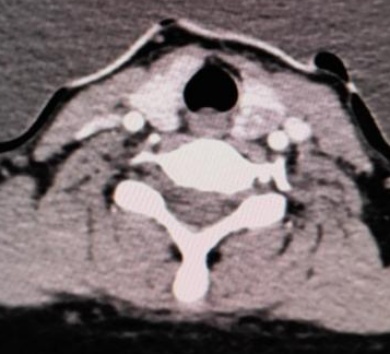

(a) (b) (c) (d)

(i) (j) (k) (l)

Figure 1. Examples of dual-energy CT arterial phase images, iodine uptake images, Rho/Z images, and pathological findings in three groups of patients with thyroid nodules (HE, ×100, H) (Rho/Z, Electron Density/Effective Atomic Number)

1. 三组甲状腺结节患者双能量CT动脉期图、碘图、Rho/Z图及病理图示例(HE, ×100, H) (Rho/Z,电子密度云/有效原子序数)